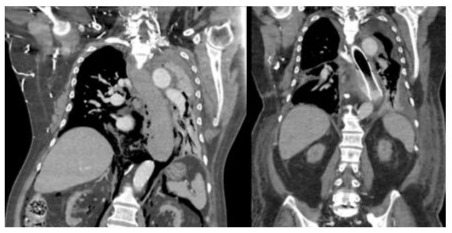

We present the case of a 66-year-old male with Spontaneous Oesophageal Perforation treated with Oesophageal Stenting. This patient reports sudden onset severe anterior chest pain after coughing and haematemesis. He has a background medical history of Type II Diabetes Mellitus, End Stage Renal Failure on Haemodialysis, Hypertension, Obstructive Sleep Apnoea and takes prophylactic Aspirin. Computed Tomography demonstrated pneumomediastinum with contamination (Figure 1). Endoscopic investigation was undertaken. This revealed multiple areas of oesophageal perforation including mucosal tears in the proximal, middle, and distal oesophagus of varying size as well as a haematoma extending the entire length of the oesophagus to the cardio-oesophageal junction (Figure 2). This endoscopy was abandoned due to respiratory compromise secondary to bilateral pneumothoraxes requiring immediate decompression with bilateral chest drains. The patient was not suitable for an oesophagectomy due to their multiple comorbidities and physiological status. The decision was made to use a WallFlex™ Fully Covered Oesophageal Stent (Boston Scientific, Mascot, NSW Australia). This stent was removed three weeks later, and gastroscopy revealed re-epithelialisation of the entire oesophagus along with complete resolution of the perforation at the mid-oesophagus (Figure 3). The patient’s dysphagia continued to improve, and his diet was progressed and discharged home.

Figure 1: Computed tomography image a) pneumomediastinum consistent with Boerrhave’s b) oesophageal stent in situ with interval improvement of pneumomediastinum.